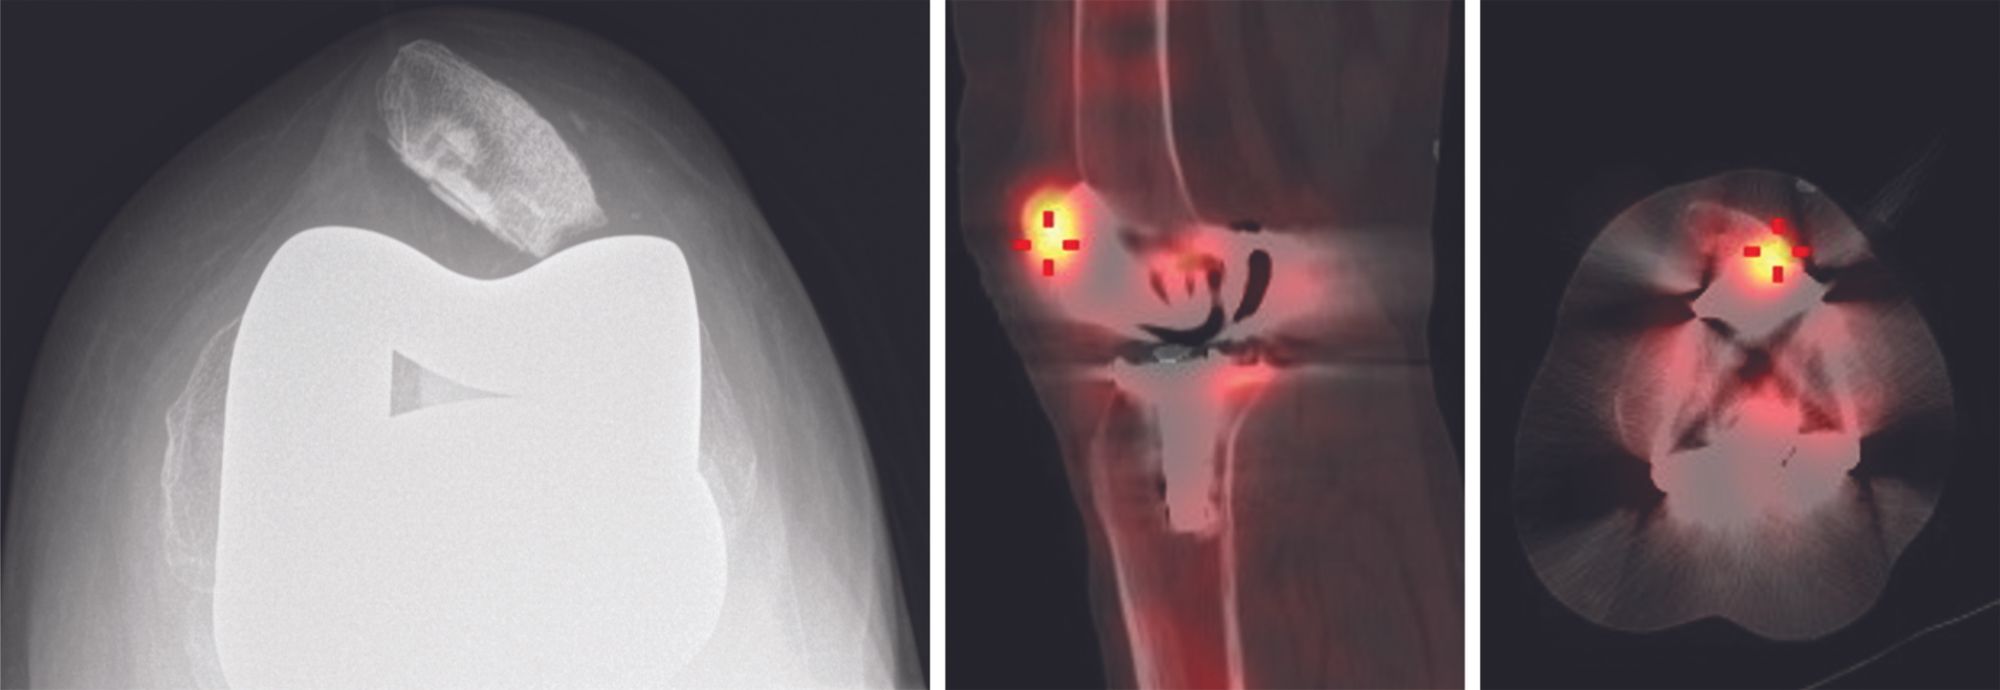

Finally, bone scintigraphy can identify patellofemoral impingement between the lateral patellar facet and femoral component, as a result of tilting. Currently our standard practice is to perform a combined CT and bone scan, such as SPECT-CT or a Tomoscan (multislice nuclear scintigraphy plus scan).

Patellar tilt is relatively common in descriptive studies.[17] It can cause painful impingement between the lateral patellar facet and femoral implant,[18] in turn due to improper patellar preparation (Figs. 3 & 4) or after medial approach with dehiscence of the capsular closure.[19]

In the specific case of painful patellofemoral impingement with a tilted or eccentric patella, solely reconstructing the MPFL can effectively recentre the patella. It may sometimes be combined with a lateral patella facetectomy to resolve the impingement and/or a lateral retinacular release to help recentre. Finally, patellofemoral instability after TKA with a native patella is a possible indication for secondary resurfacing. Persistent patellar instability during the procedure should prompt the surgeon to use one of the procedures described above.

Our indications for MPFL reconstruction in TKA are selective and restricted to patellar instability, eccentricity or tilt, where the implant was initially correctly positioned (Fig. 11). It is important to understand that any soft tissue procedure will fail over time without correcting the malpositioned components. During revision surgery for malposition of the components additional MPFL might be helpful.